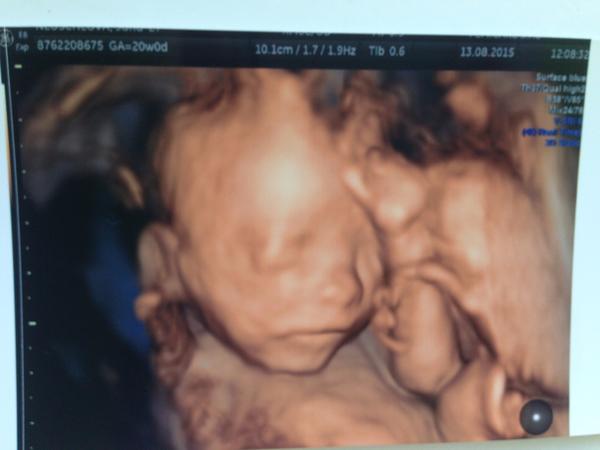

@gabuchah ňuňuška krásna malinká 🙂 pridávam aj našú foto z 20. tt

@55minnie55 krásna, ako si ležká 🙂 to je zlaté 🙂 vaša teda viac spolupracovala 🙂